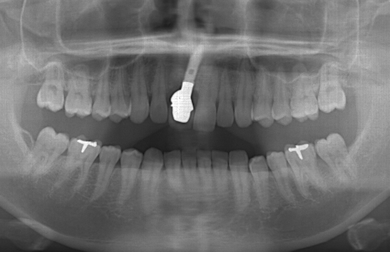

インプラントの症例写真 IMPLANT

| 治療方針 | 抜歯と同時にインプラントを埋入することにより、治療期間を大幅に短縮させる。 | ||||||||||||||||||||||||||||||||

| 治療内容 | インプラント1本(抜歯即日スピードインプラント)、メタルボンドセラミック1本 | ||||||||||||||||||||||||||||||||

| 総治療費 | 451,500円 | ||||||||||||||||||||||||||||||||

| 治療期間 | 5ヶ月 |